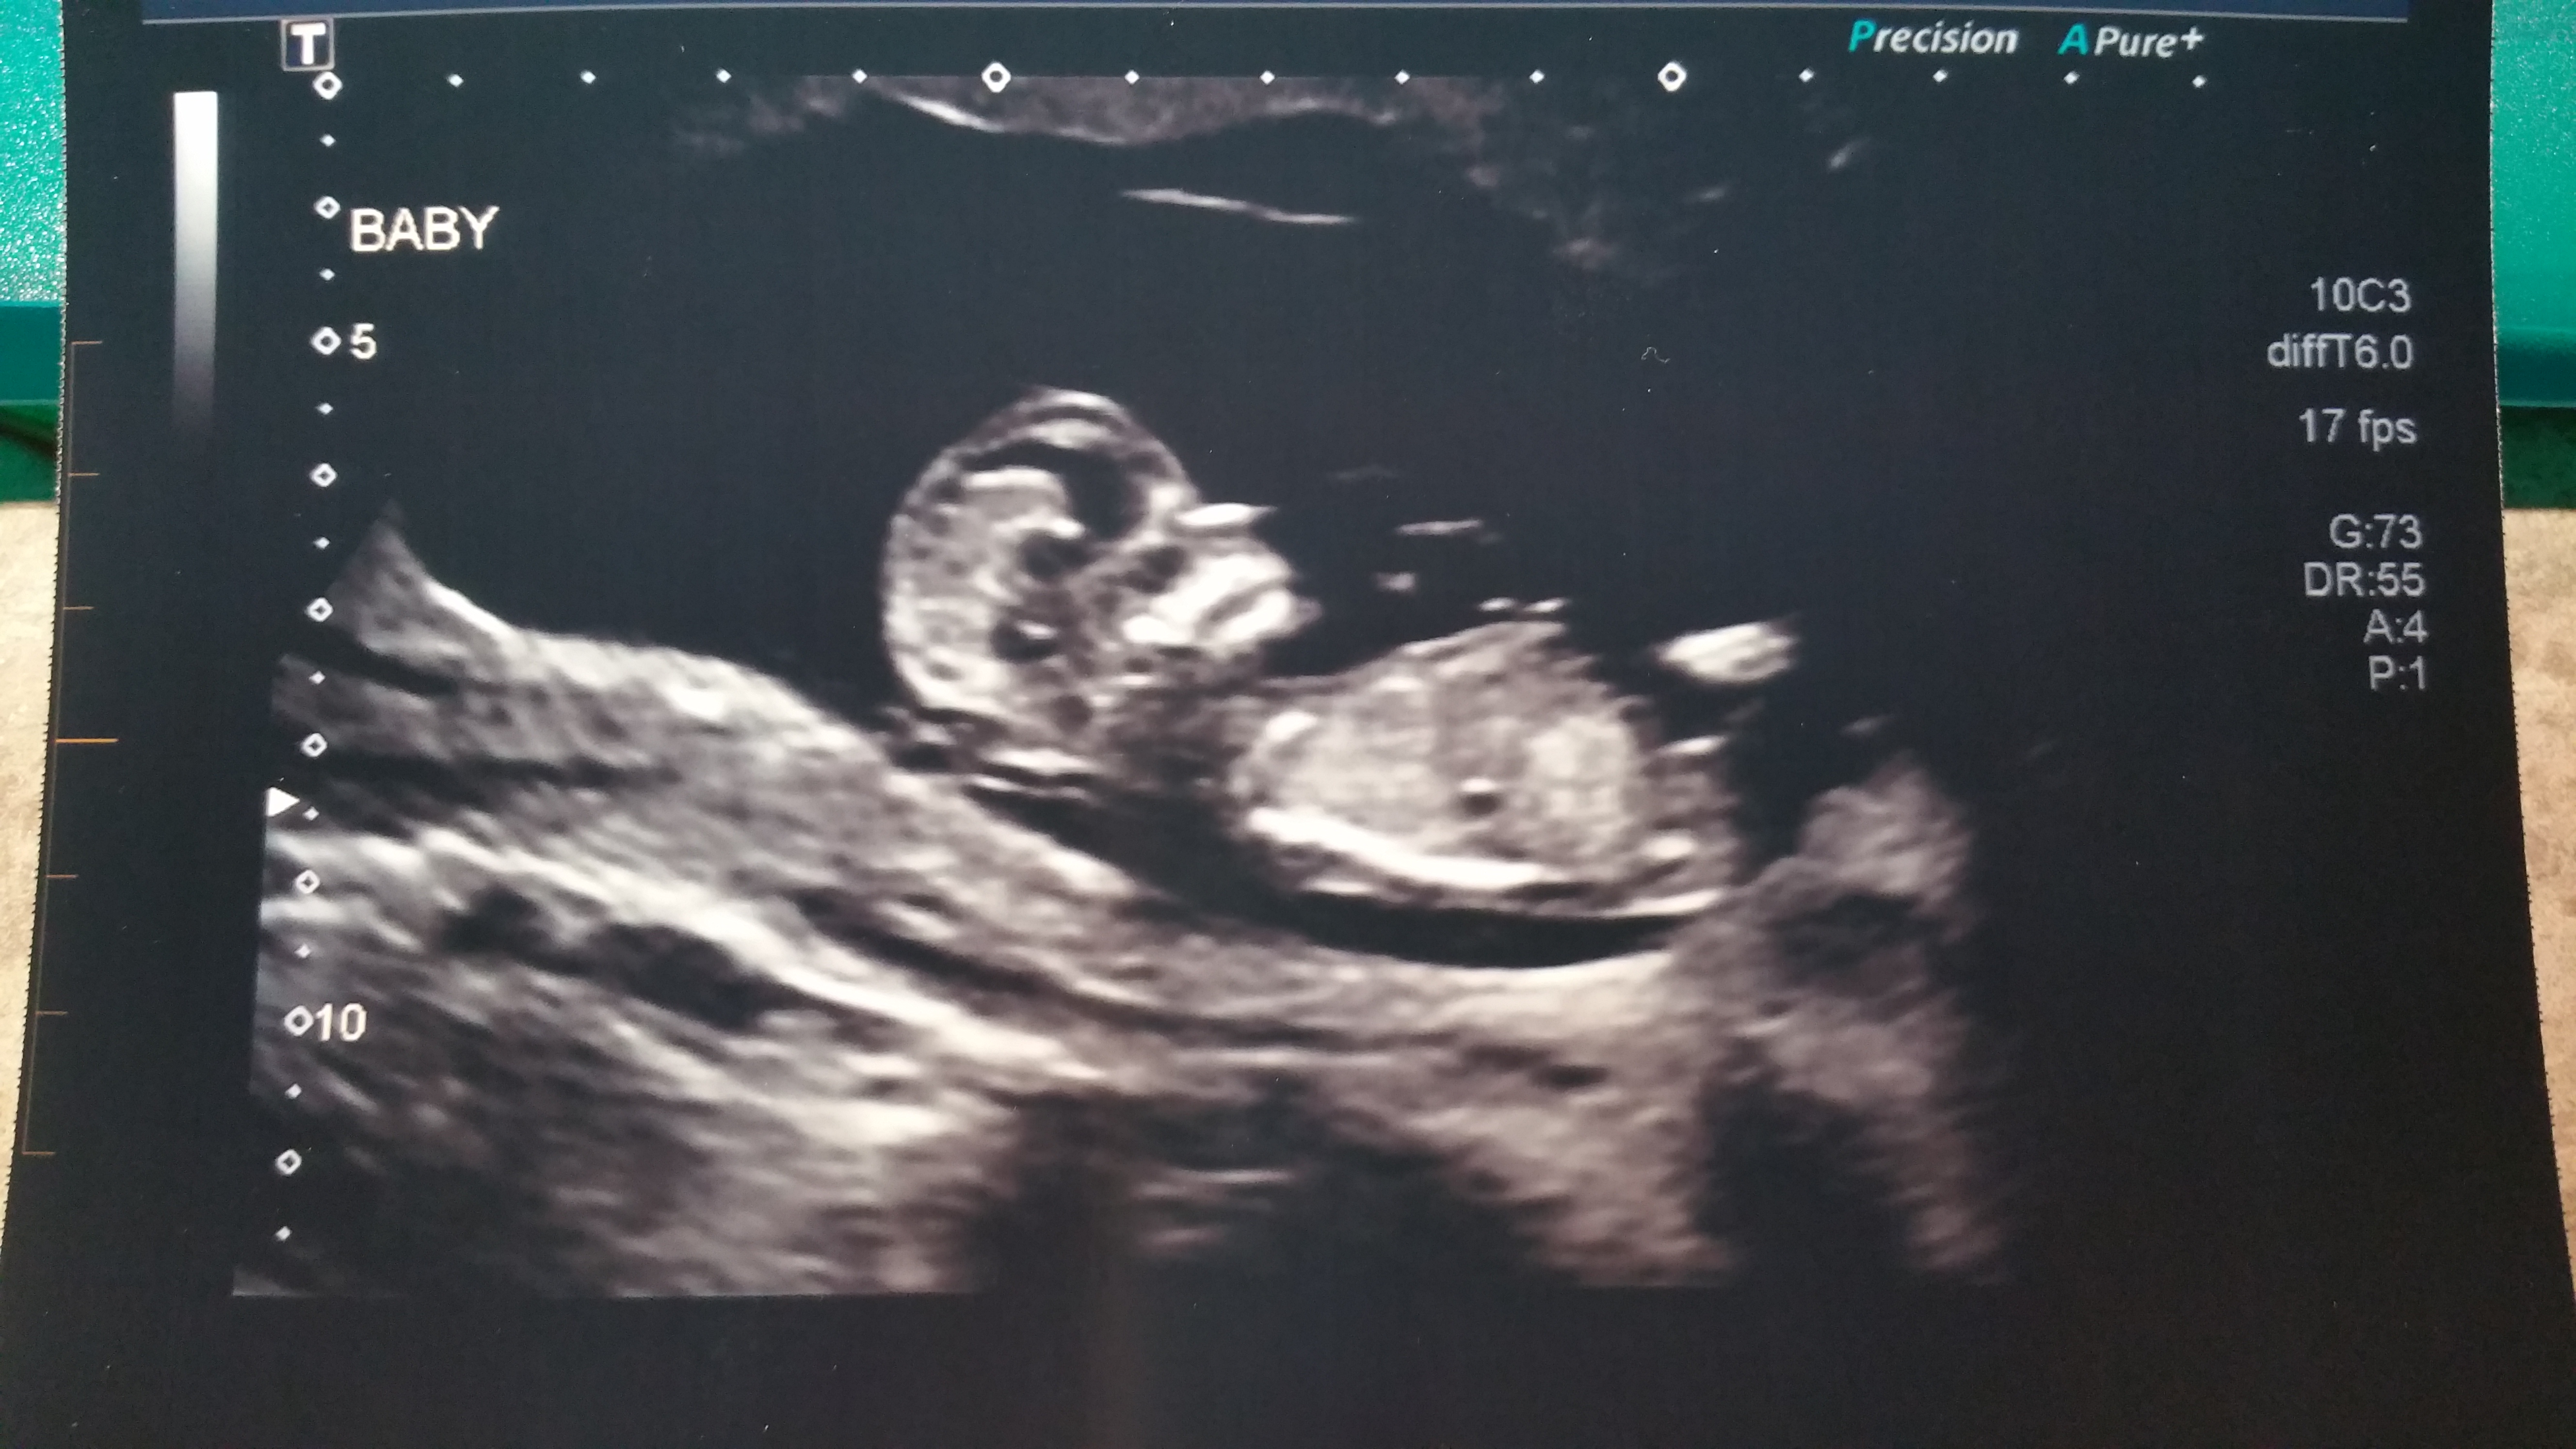

Absoultley a girl!!! I would be shocked if you said it was a boy .Please keep me informed

Thank you! So I am really confused...I understand that it's on the left side of the picture, but isn't that the right side of my uterus? That's how it was explained on a blog I read (see pic below...this is explaining for a transvaginal ultrasound). Can you help me understand? As I understand it, you are supposed to hold the picture to your belly upside down (to you, right side up to someone looking at you) and that will show you what side of your body it's on. So as I interpret it, it would be a boy...